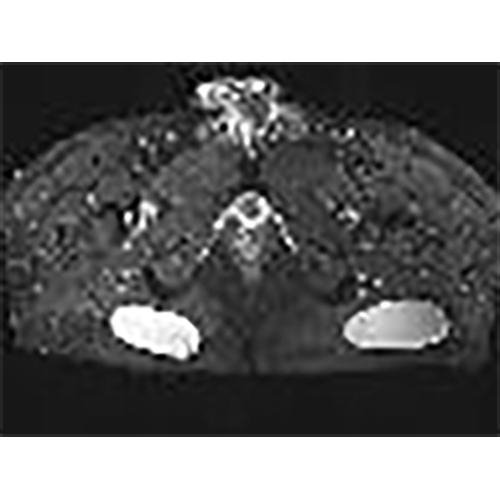

For this case, which will be detailed further, an MRI IS MANDATORY to check the depth as the position of the implants before opting for an indication or an absolute contra indication.

For this case, an MRI IS MANDATORY to check the depth of the implants in case the patient is very thin.

implants are 102x92x34 big,and position between skin and muscle on depth from the skin 16,7mm